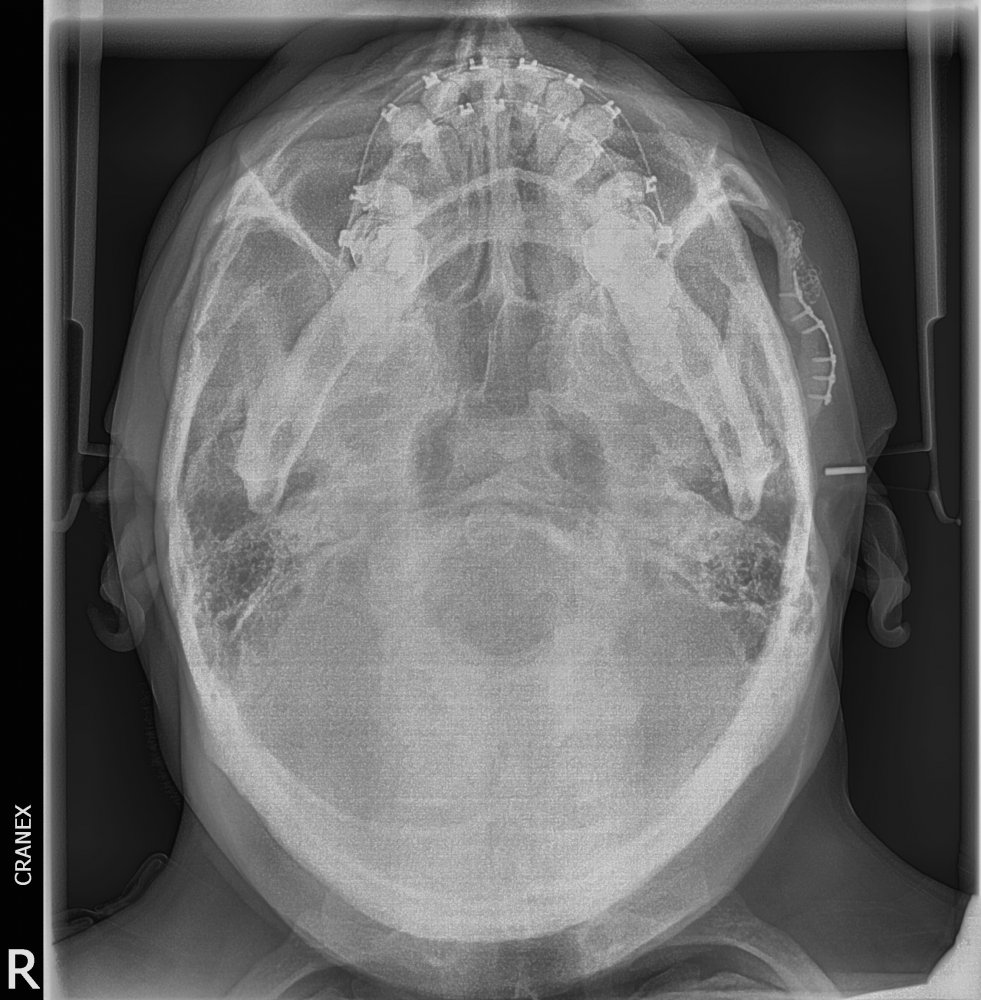

- RX .Inversa de Towne